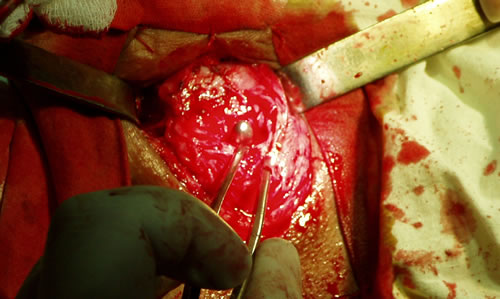

Виден буж, введенный в проксимальный отрезок уретры через

надлобковый свищ

Удаление рубцовых тканей

Виден буж и края бульбозного отдела уретры